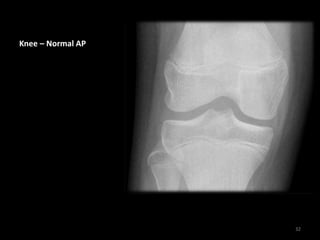

Knee – Normal AP

32

• This x-ray showing the

cartilage ( hyaline ) ,

meniscus and joint soft

tissue.

• We can not specific any

abnormality for knee

components unless we

request MRI for the

patient.